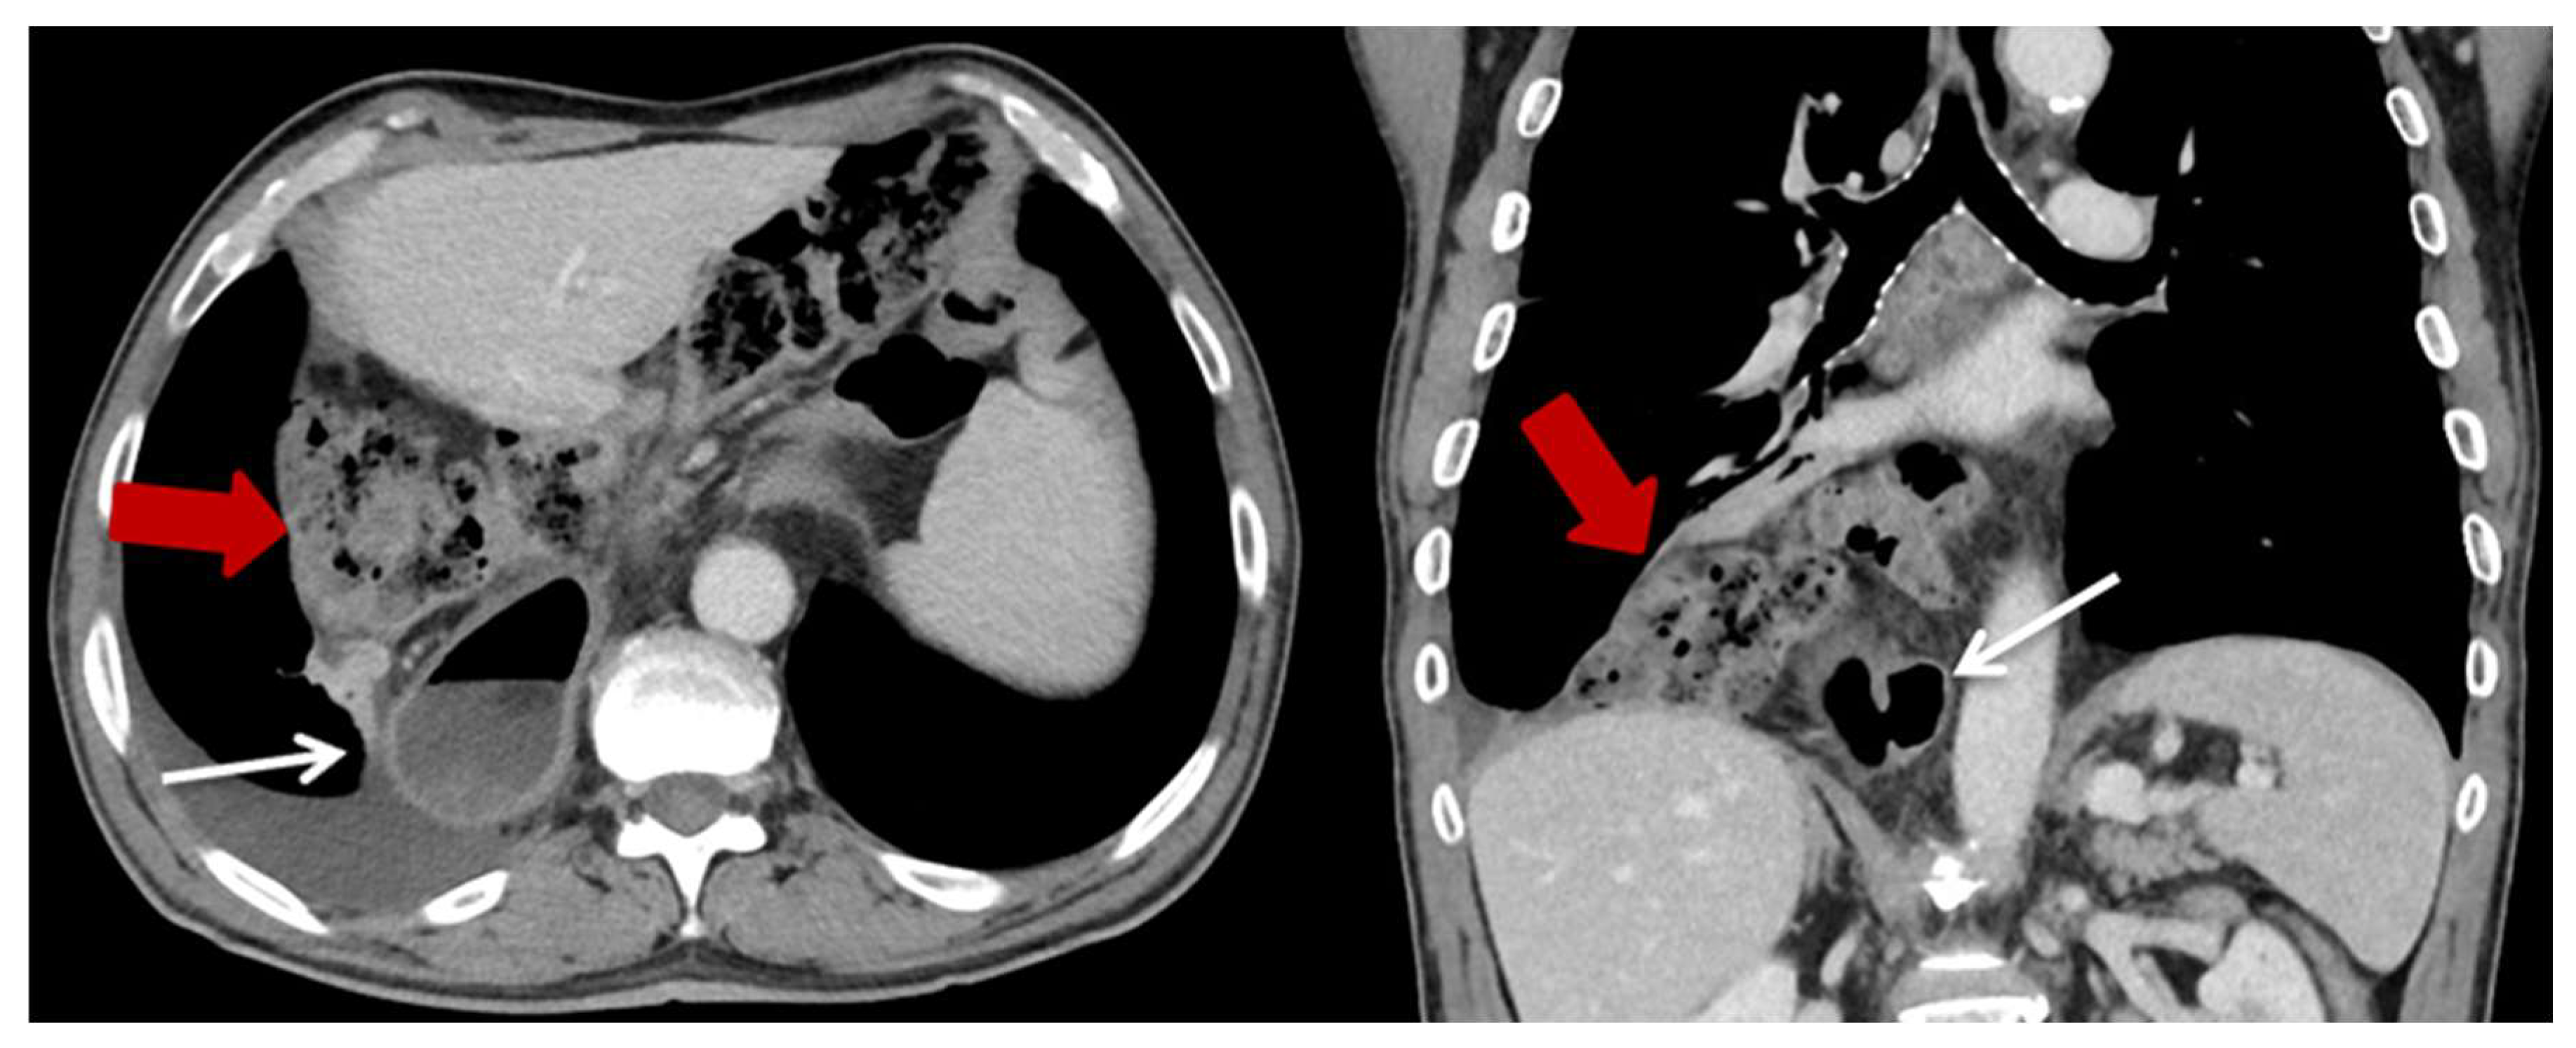

| Characteristics | HH (n = 23) (%) |

|---|---|

| Content of HH, n (%) | |

| Colon | 23 (100) |

| Additionally small bowel | 3 (13) |

| Position of the HH n (%) | |

| Left thoracic side | 18 (78.3) |

| Right thoracic side | 1 (4.4) |

| Both sides | 1 (4.4) |

| Lower mediastinum | 3 (13) |

| Symptoms n (%) | |

| None | 13 (56.5) |

| Abdominal pain and discomfort | 10 (43.5) |

| Ileus/incarceration | 4 (17.4) |